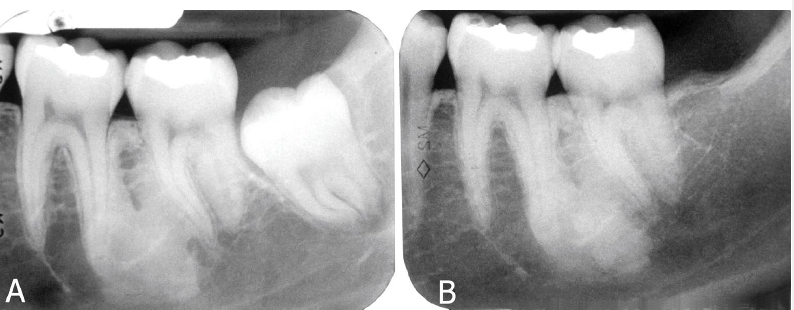

idiopathic osteosclerosis differential diagnosis

contrast with condensing osteitis

if the tooth is non vital - condensing osteosis

condensing osteitis

features of condensing osteitis

non-vital tooth or presence a source of inflammation

widened PDL

sclerosis of bone around roots in response to chronic inflammation

may mimic idiopathic osteoscerosis